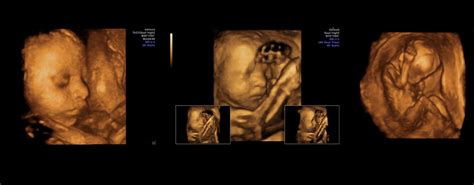

Ecografii

Sunt programate trei ecografii standard, decontate de INAMI:

- Trimestrul 1 (săptămânile 11-14): Se evaluează vitalitatea fătului, ritmul cardiac, dimensiunea și se efectuează primul examen morfologic, inclusiv măsurarea translucenței nucale.

- Trimestrul 2 (săptămânile 20-24): Ecografia "morfologică" oferă o analiză detaliată a anatomiei fetale, cordonului ombilical și placentei.

- Trimestrul 3 (săptămânile 30-34): Se verifică creșterea fătului, poziția sa și funcționarea organelor.